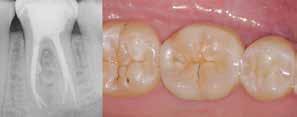

Ricostruzione post-endo fase finale della terapia endodontica che prevede l’esecuzione di un corretto restauro coronale, con un sigillo marginale che prevenga la ricontaminazione batterica dell’endodonto e del periapice, e che protegga l’elemento ricostruito dagli stress masticatori.

L’obiettivo finale della terapia endodontica è rappresentato dalla completa sigillatura degli spazi canalari, con la massima estensione sia in senso apicale che laterale.

Consiste nel creare un sigillo ermetico tridimensionale, stabile nel tempo, in grado di isolare e neutralizzare i microorganismi sopravvissuti alle precedenti procedure di sagomatura e detersione, “murandoli” sulle pareti canalari e all’interno dei tubuli dentinali.